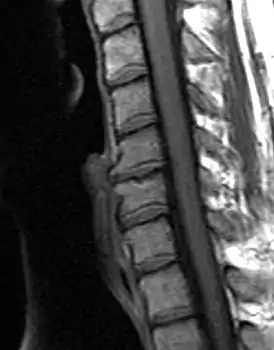

![]() Дегенеративно-дистрофическое заболевание диска, C5-C6 с остеофитами | |

Типичными рентгенографическими данными ДДЗД являются черные диски, сужение дискового пространства, вакуумные диски, склероз конечной пластинки и образование остеофитов[2][3].